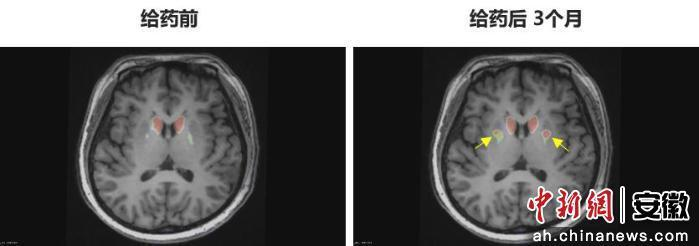

今年6月,李女士在中國科學技術大學附屬第一醫院接受了NCR201干細胞移植治療,該療法利用誘導多能干細胞(iPSC)衍生的多巴胺能神經前體細胞。三個月后,她成為全球首例“功能性治愈”的帕金森病患者。

“身體不僵硬了,像正常人一樣?!崩钆啃χf。多年的抖動與“關期”徹底消失,她重新感受到身體的輕盈和心靈的自由。術后影像顯示,移植細胞已在腦內成功定植并發揮功能,醫生稱這些“亮點”是新生多巴胺能神經元的直接證據。

圖為李女士 PET-DAT/MRI融合圖像術前與術后三個月對比。

圖為李女士?PET-DAT/MRI融合圖像術前與術后三個月對比。